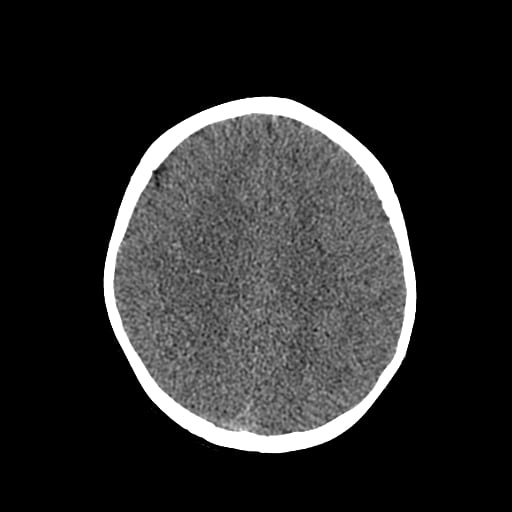

Age: 1

Sex: Male

Indication: Fall